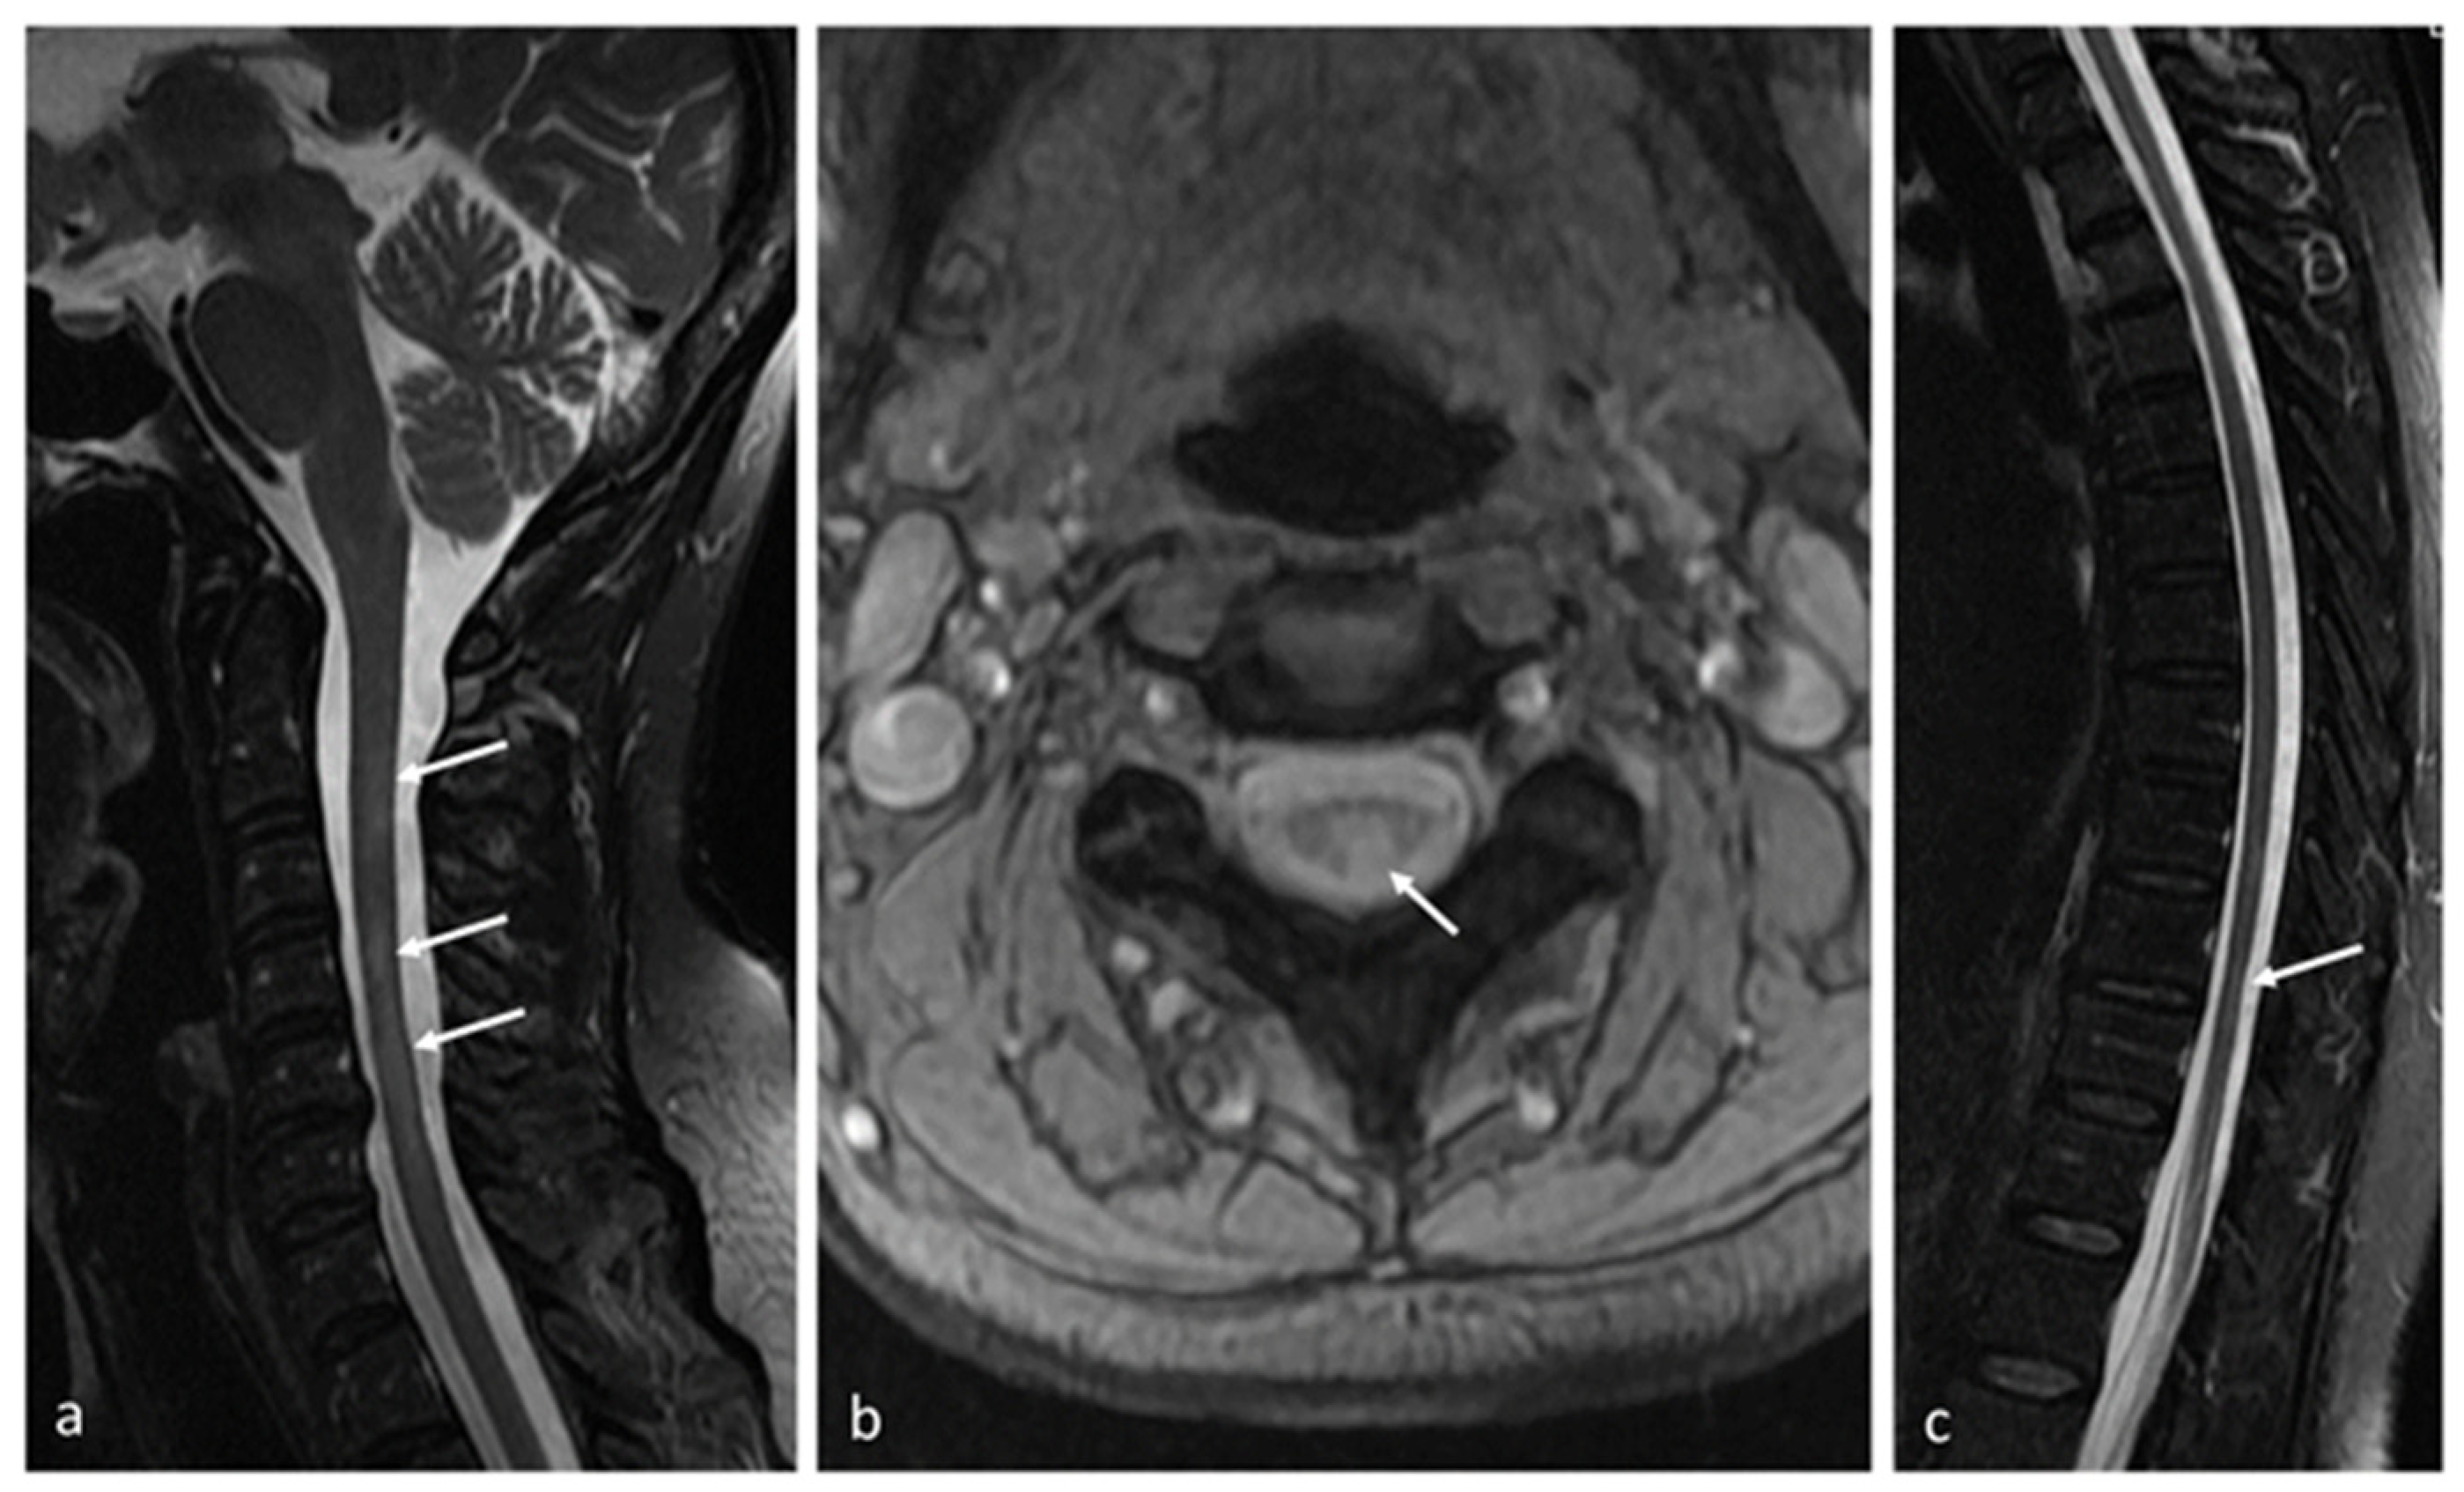

- Siger, M. Magnetic Resonance Imaging in Primary Progressive Multiple Sclerosis Patients: Review. Clin. Neuroradiol. 2022, 32, 625–641. [Google Scholar] [CrossRef] [PubMed]

| Radiological (MRI) | SEL | constant and concentric volumetric expansion in T2, with concurrent reduction in T1-weighted sequence, revealed in subsequent 2–3 MRI scans | specific demyelinative lesions–sites of chronic inflammation | [96,97,98,99,100] |

| PRL | typical rim surrounding at least 75% of lesion, which reflects the layer of iron-laden microglia and macro-phages, accompanying demyelination and axonal transection (phase imaging, SWI or multi-gradient echo sequences) | specific demyelinative lesions—sites of chronic inflammation | [96,97,98,99,100] | |

| cortical lesions | visualization of cortical damage and ribbon-like subpial demyelination (ultra-high magnetic field resolution (>7 T) | chronic neuroinflammation | [96,102,103] | |

| measures of global and regional CNS atrophy | loss of cerebral structure volume | diffuse neurodegeneration with axonal loss | [100,101,102,103,104,105] | |

| “dirty-appearing white matter” | ill-defined hyperintense areas, located mainly around the lateral ventricles | diffuse neuronal damage with chronic inflammation | [104,106] | |